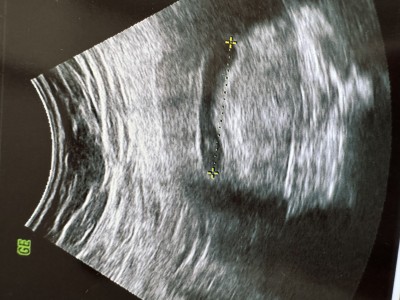

7 hafta 6 gunluk kesem büyük olduğunu söyledi doktorum bebek çok küçük 4 mm olduğunu söyledi kalp atışları zoraki var yok arası duydum bu durumu yaşayan var mı

Gebelik haftası 8